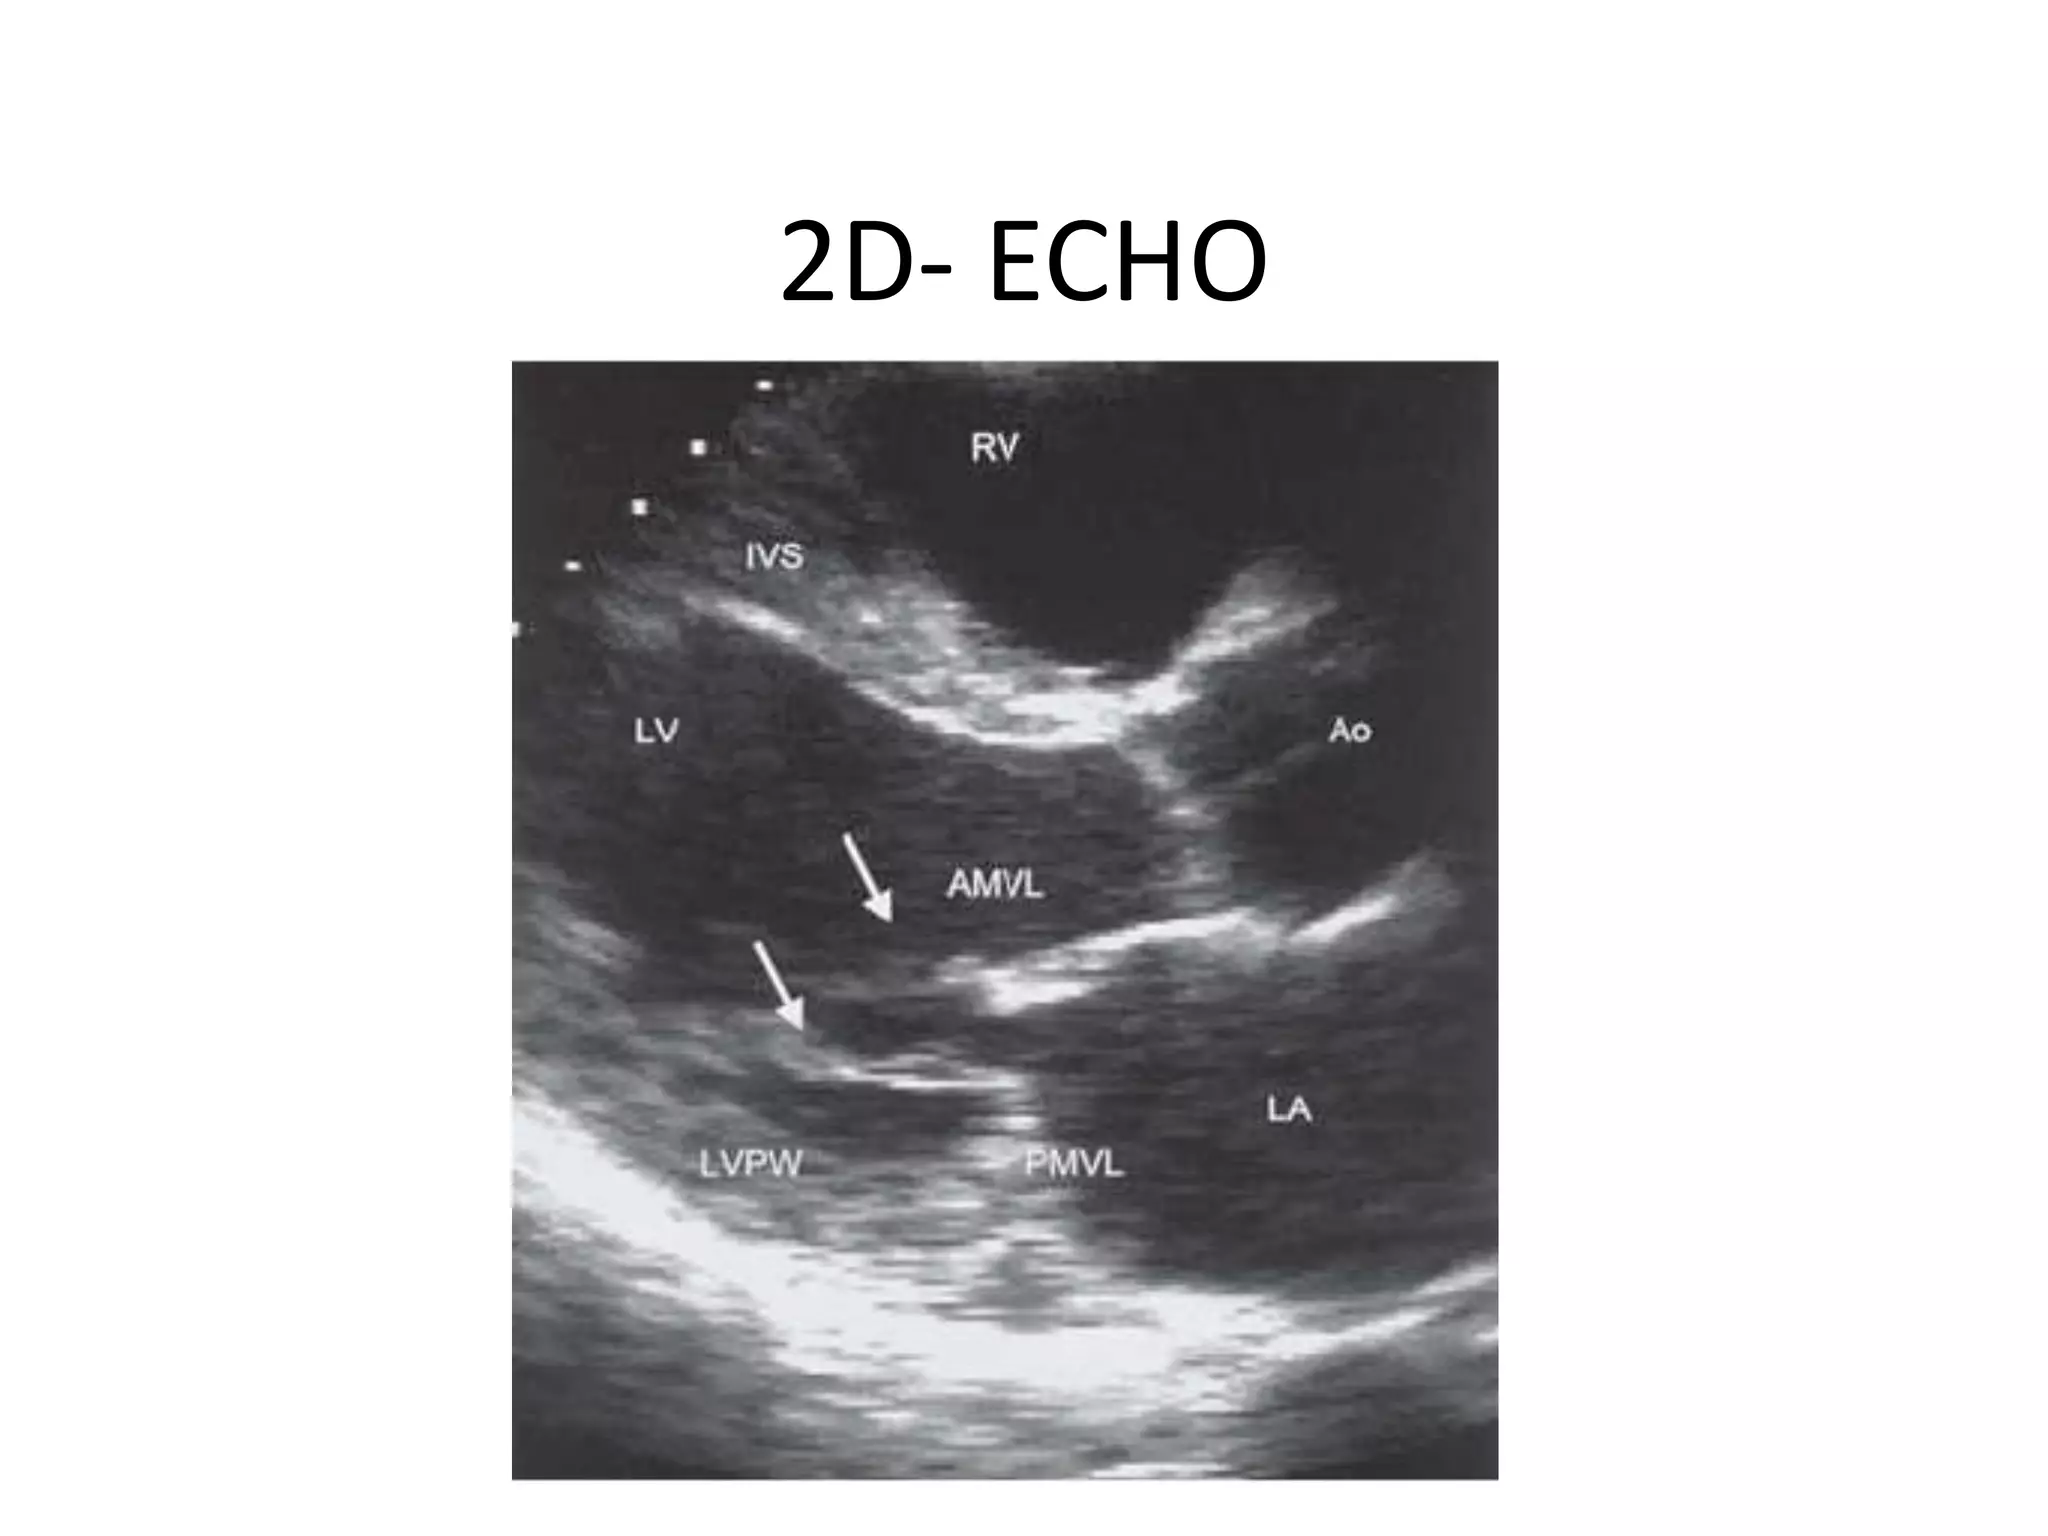

2D- ECHO

ECHO TECHNIQUES Three echomethods are in common clinical usage: • Two-dimensional (2-D) or ‘cross-sectional’ • Motion or m-mode • Doppler – • Continuous wave, • Pulsed wave and • Colour

Summary Of EchoModalities And Their Main Uses 2-D echo • ● Anatomy • ● Ventricular and valvular movement • ● Positioning for m-mode and doppler echo M-mode echo • ● Measurement of dimensions • ● Timing cardiac events Pulsed wave Doppler • ● Normal valve flow patterns • ● LV diastolic function • ● Stroke volume and cardiac output. Continuous wave • ● Severity of valvular stenosis • ● Severity of valvular regurgitation • ● Velocity of flow in shunts Colour flow mapping • ● Assessment of regurgitation and shunts.